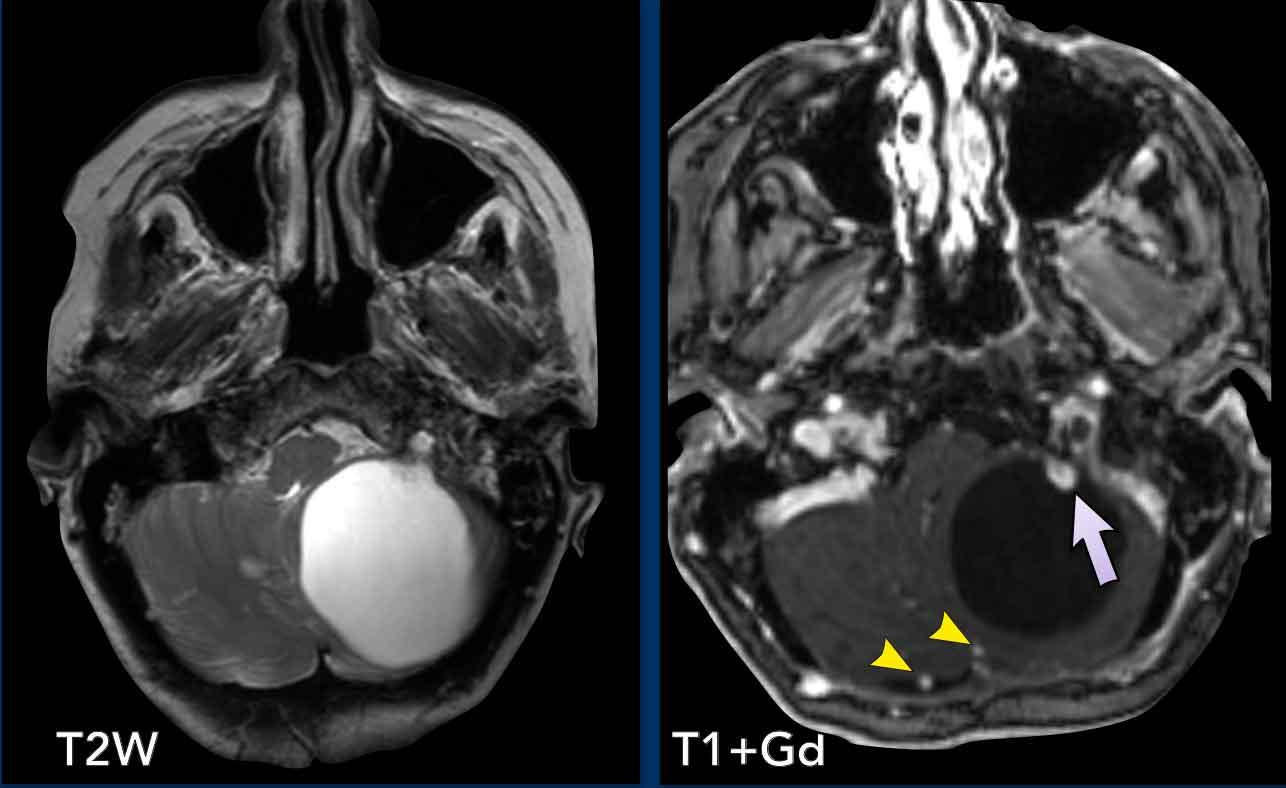

Các hình ảnh này của một nam giới 29 tuổi.

Hình ảnh

Tổn thương dạng nang với thành không ngấm thuốc và một nốt ngấm thuốc nằm ở phía màng mềm.

Kết luận

Hình ảnh điển hình của u nguyên bào mạch máu.

Khi phẫu thuật cắt bỏ khối u này, phẫu thuật viên chỉ cần lấy bỏ phần nốt.